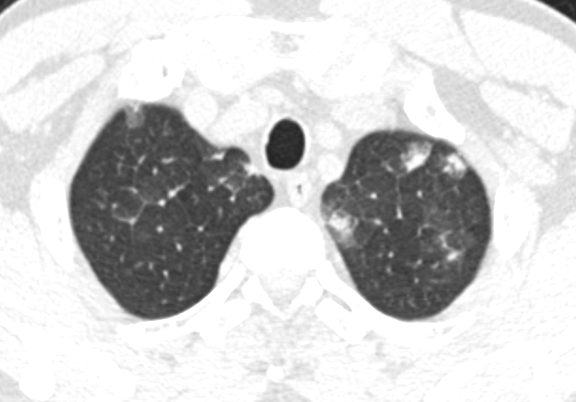

Bệnh nhân được khám và xét nghiệm cho thấy bạch cầu máu tăng cao trong đó tăng chủ yếu thành phần bạch cầu ưa acid và kèm theo tổn thương phổi là những đám mờ rải rác 2 bên trường phổi.

H́nh ảnh chụp phổi của bệnh nhân với nhiều đốm sáng là ấu trùng giun chui vào phổi. Ảnh BVCC

Bệnh nhân được nghi ngờ nhiễm hội chứng Loeffler, được xét nghiệm về giun sán thấy (+) với giun đũa (Ascaris) và giun lươn ( Strongyloides).

Bệnh nhân đă được điều trị bằng thuốc tẩy giun đặc hiệu. Sau 2 tuần bệnh nhân hết hoàn toàn triệu chứng, bạch cầu ưa acid trong máu giảm nhiều, tổn thương trên phim chụp gần như biến mất.